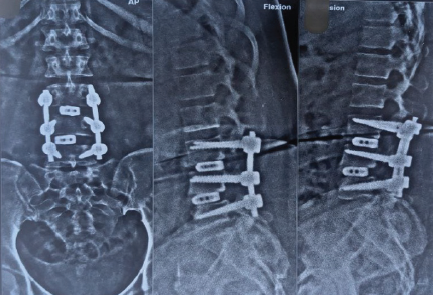

Postoperative plain radiographs (anteroposterior and lateral views) and CT imaging were obtained on postoperative day 2, which at that time appeared acceptable, though the quality was limited by streak artifact from metallic implants. In 1 week, x-ray was taken as shown in Figure 2.

Anteroposterior radiograph demonstrated:

– Left-sided L4 pedicle screw clearly projecting outside the lateral border of the L4 vertebral body, consistent with screw cut-out

– Bilateral L3 pedicle screws malpositioned, with both screws demonstrating medial perforation through the vertebral body

– Progressive loss of fusion correction at L3-L4 with restoration of slip to approximately 30% (compared to preoperative 50% slip, representing improvement but still significant)

– Loss of intervertebral height at L4-L5 compared to immediate postoperative films

Lateral radiograph revealed:

– Sagittal malalignment with loss of lordotic correction at the fused levels

– The L4 left screw visualized in cross-table lateral view demonstrated substantial cranial migration out of the L4 pedicle with the screw tip lying within the spinal canal

– Evidence of hardware subsidence into the vertebral bodies